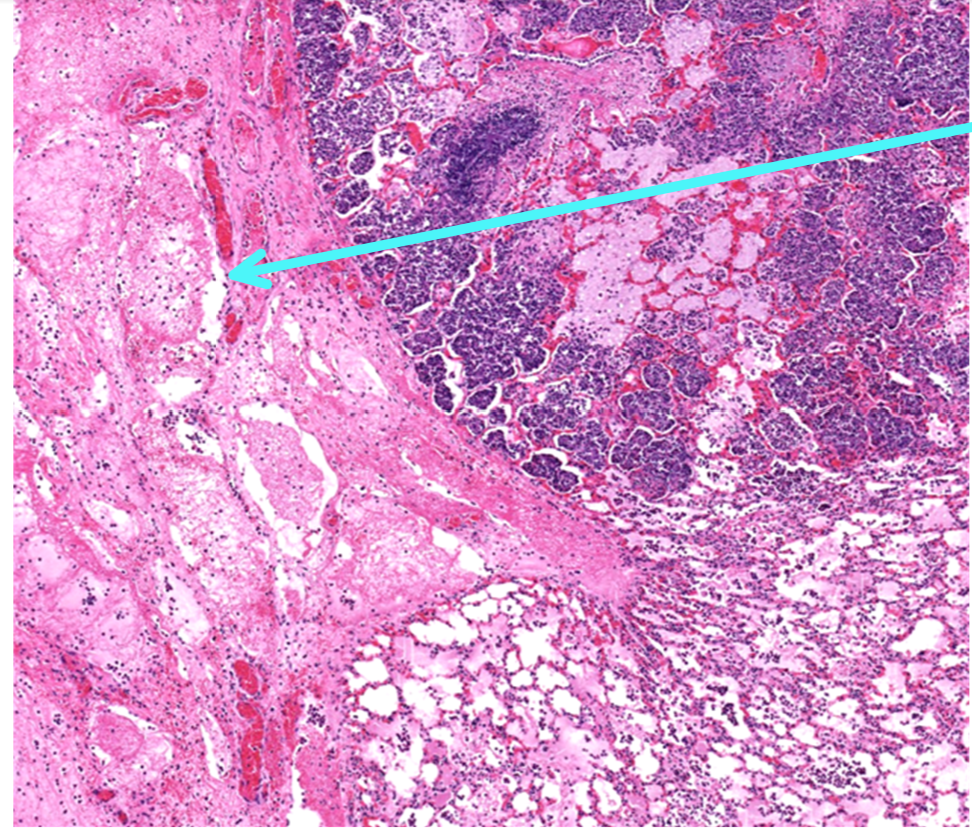

This is a slide from a bovine lung.What would the cellular exudate be composed of in this lesion?

macrophages, neutrophils, and necrotic alveolar epithelium

This is from a bovine lung. What is the histomorphologic diagnosis for this lesion?

acute fibrinopurulent bronchopneumonia

Identify this structure:

neutrophils

fibrin

Q

interlobular lymphatics with fibrin and hemorrhage

fibrin thrombi